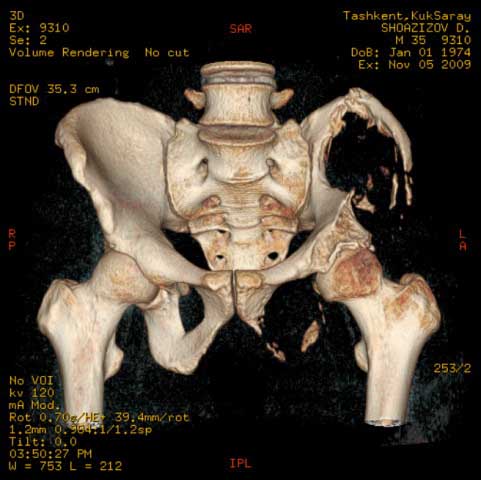

Могу пока выложить еще снимки и показать хронологию данного процесса и его прогрессирование, первый снимок был 2011 года. Вот этот 2009

Также структуру поражения кости можно увидеть на обычных рентгенограммах таза или Компьютерно-Томографических срезах. Трехмерные снимки, кроме красивой картины, не добавляют информации, и самым главным информативным является МРТ, которая покажет структуру ячеек.